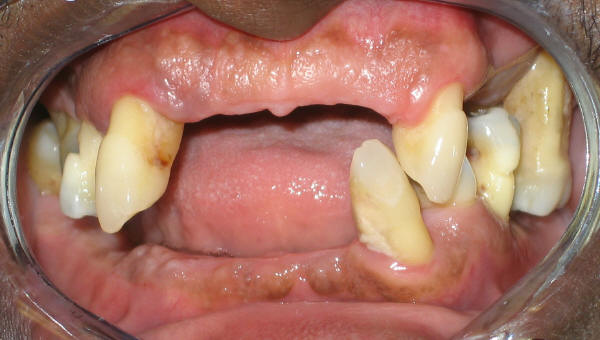

| 圖一:牙齒已經保留不了,需要全部拔除 | 圖二:拔牙后立刻戴上假牙,病人高興極了 |

拔牙后牙槽骨發生吸收,牙齦退縮,這一過程需要一到兩個月才能穩定,橋或者活動局部義齒製作還需要半個月到兩個月。如果您失去上前牙,可能不願意等那麽久。針對這個問題,醫生在拔牙(圖一)之前取模,送到牙科技工室製作臨時即刻義齒(活動,immediate denture),拔牙后您就可以馬上戴上臨時義齒,外觀得到改善(圖二)。臨時義齒還有其它好處,它可以起到術後止血作用,它可以給您一個機會判斷您是否喜歡活動義齒,如果您實在不習慣活動義齒,您還有選擇橋或種植牙餘地。如果您最後還是選擇活動局部義齒,臨時義齒可以留著備用,活動義齒像任何一個身外之物如眼鏡容易丟失。臨時義齒所用材料不是最好,容易坏,不適合長期使用。